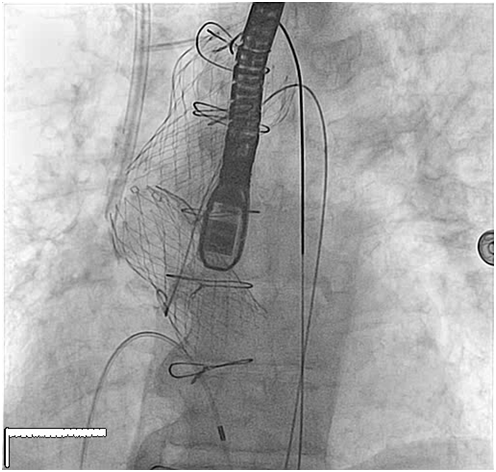

79 y old male patient, known to have diabetes mellitus, end stage renal failure and chronic obstructive pulmonary disease, this patient had aortic valve replacement (AVR) 15years prior, but because of infective endocarditis 7years ago, he underwent a redo AVR (Aortic valve Bioprosthesis) using a 25mm cry preserved aortic homograft implanted as a full root in another hospital. Patient was admitted with severe heart failure and pulmonary edema. His Echocardiogram showed severe AR (Figure 1). Patient was treated aggressively with anti-failure medications. The case discussed in heart team and both options AVR vs TAVI were raised in this high risk patient, with STS score 18. Both the heart team and Family preferred TAVI, According to sizing application this homograft valve will fit with Size 29mm Core Valve, The CT-scan measurements showed an aortic annulus size 21-25mm at different level, Perimeter range from 71-73, 3mm, Aortic valve area 2.9 cm2, and a heavily calcified a tube-like aorta (Figure 2). No clear sinus or junction was seen by CT. A trans-femoral approach for Valve in Valve was used. A 29 mm Medtronic Core valve was deployed and the landmark was the calcium in the root. Unfortunately, it migrated up-ward most probably due to the rigidity of the homograft tube and no real narrowing or calcified leaflet to anchored the valve (Figure 3). Therefore we used another 29 core valve and deployed it through the first one which was well seated in ascending aorta as support. This method of support was very successful for final deployment (Figure 4). It was similar to the melody valve deployment in treating pulmonary regurgitation. There was no aortic regurgitation by Echocardiogram (Figure 5). Patient was very stable and discharged home after 48hours.

Figure 4 Final depolyement of Valve in valve , showed how the second valve was will supported by the first valve.